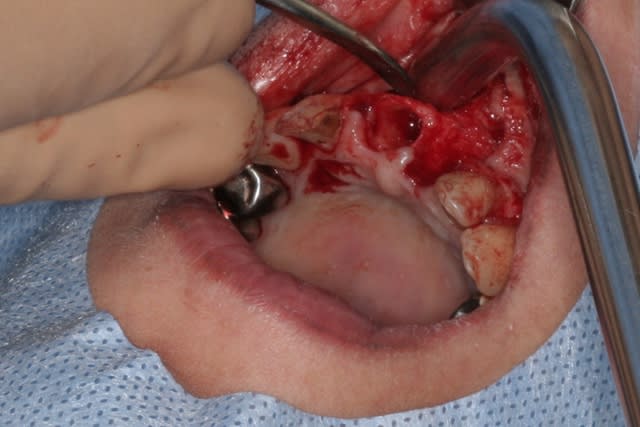

Purée, tu prends des risques énormes en fourrant ton bio oss puis en vissant les implants dans la masse de bio oss, de un, et sans membraner l'interface pilier implant, de deux...

Je suis peut-être vieux jeu mais c'est, à mon avis, dangereux d'un point de vue bactériologique.

c'est pas la première fois que je fais çà...;-)

et çà me donne plutôt de bons résultats

après tout...le périoste n'est-il pas la meilleure membrane?

par contre il faut veiller à avoir une bonne étanchéité au niveau des sutures...